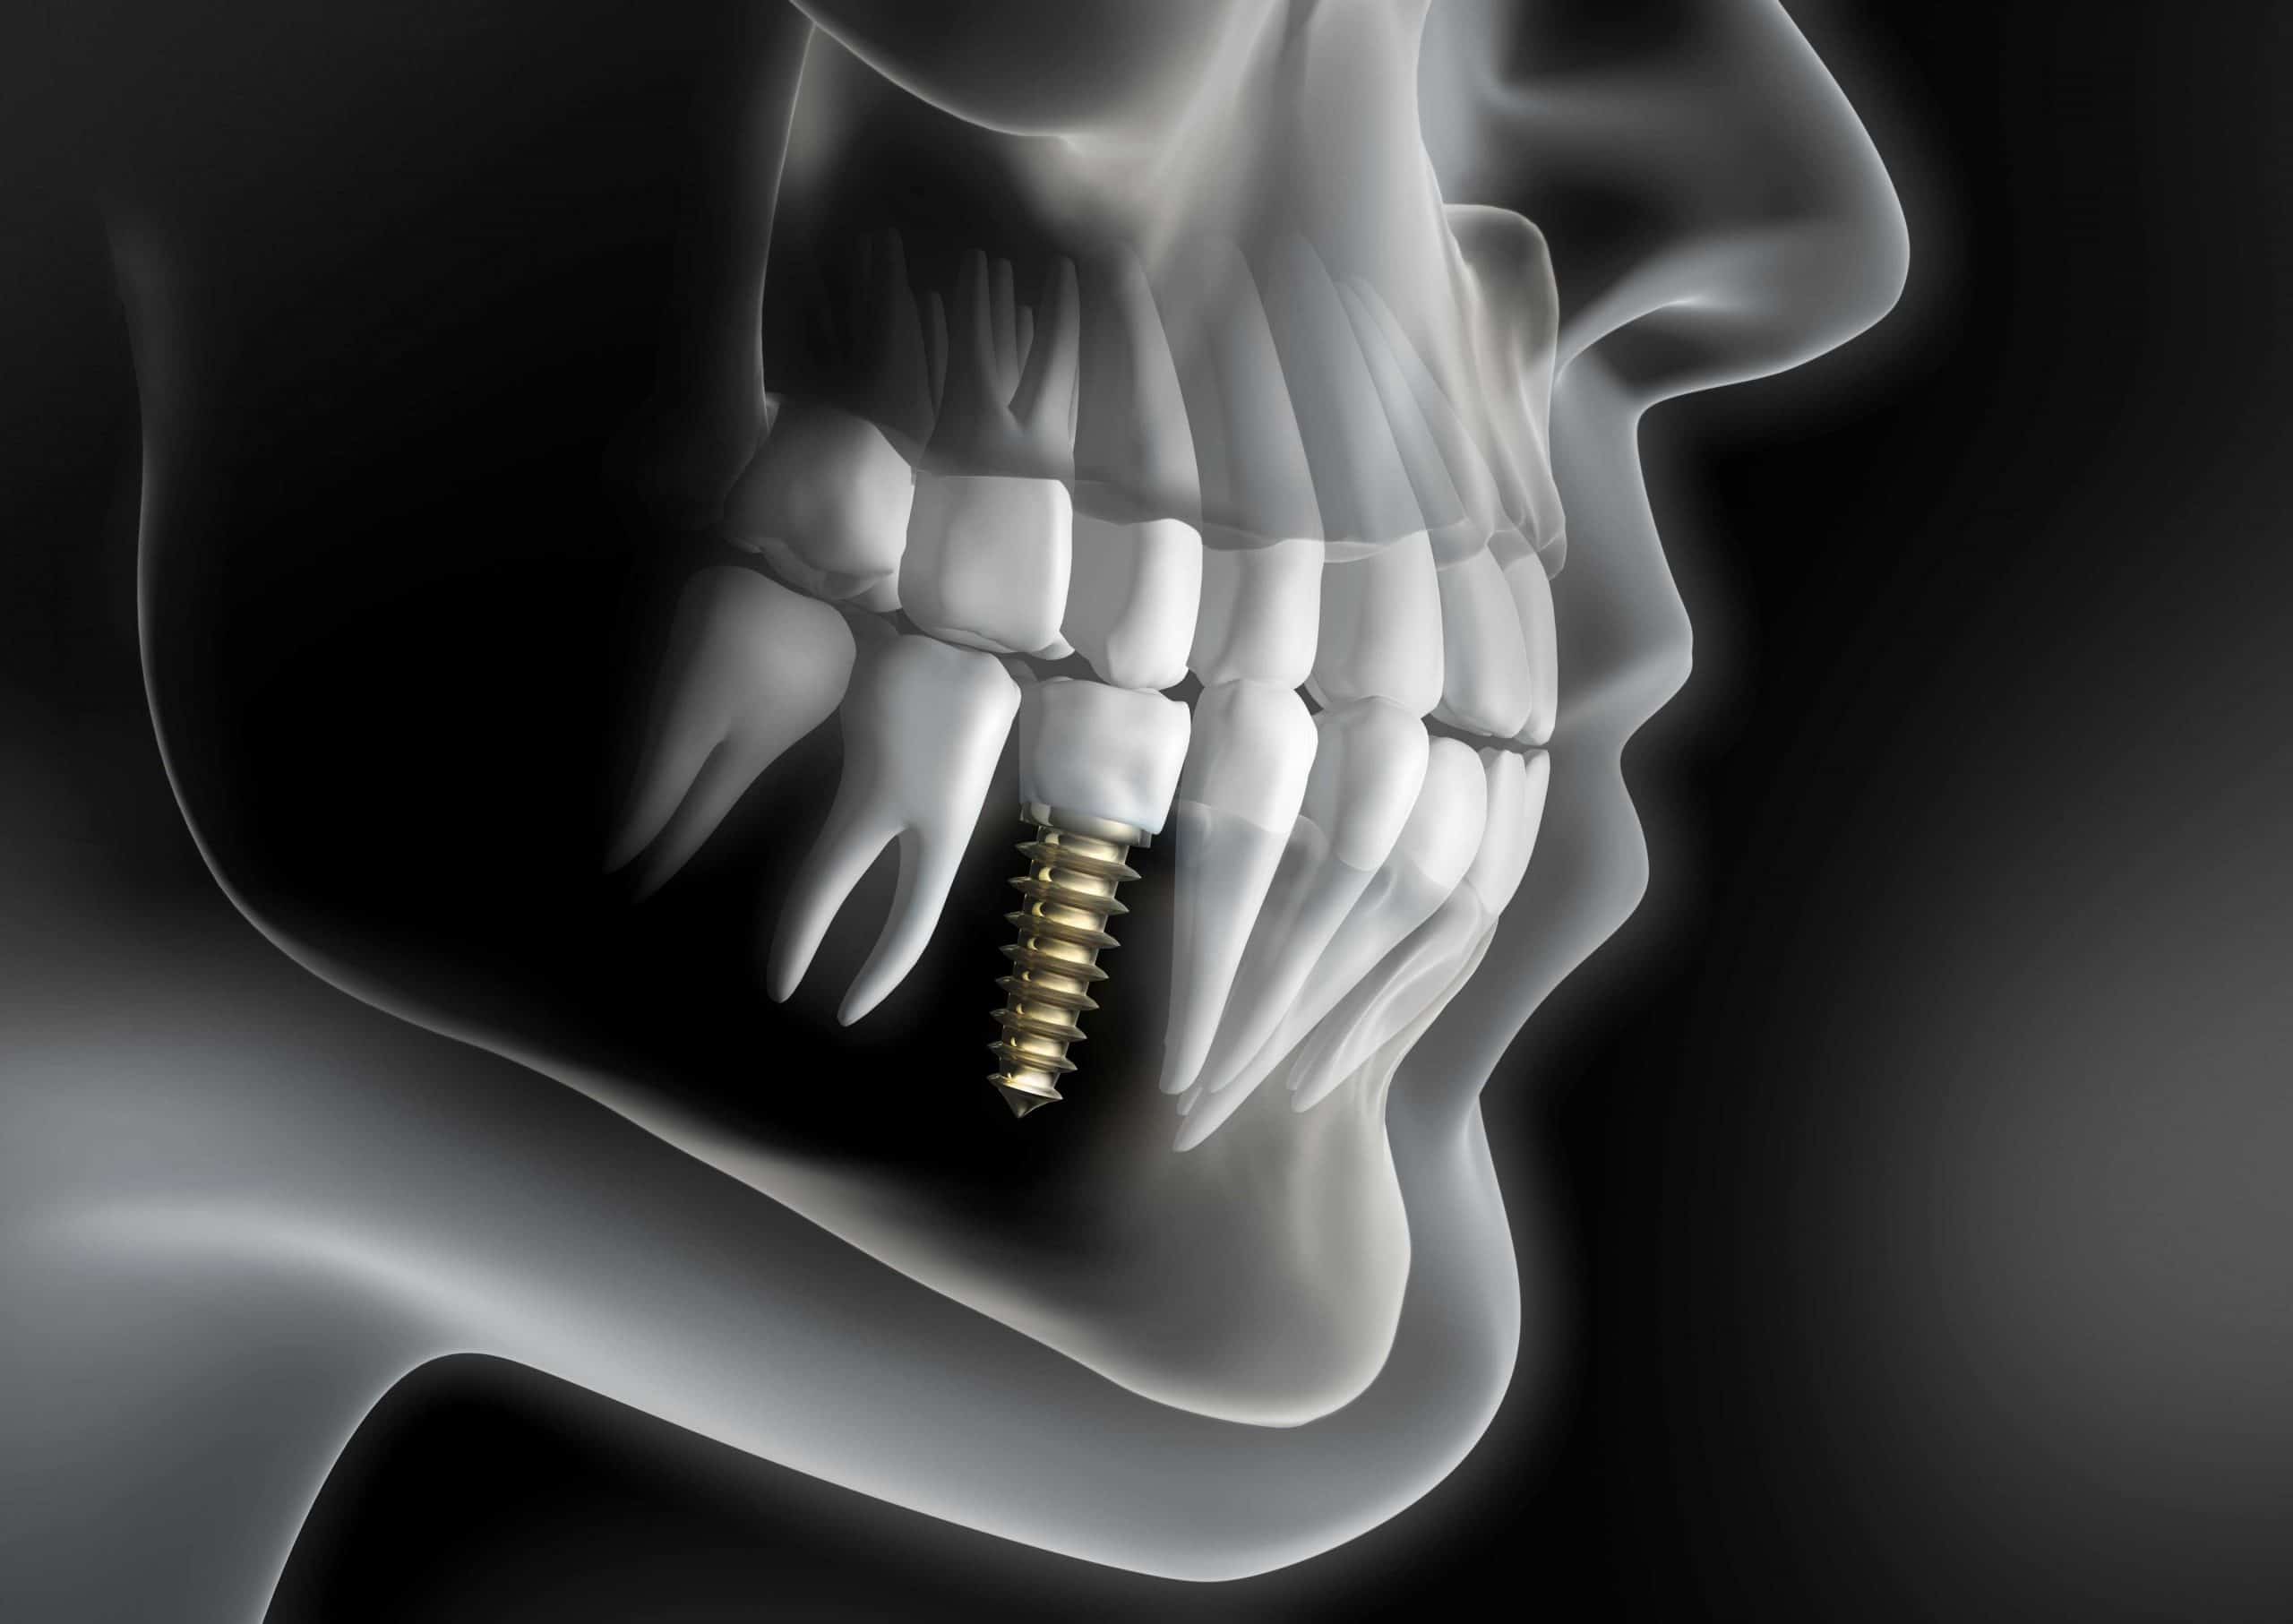

Зубы на черном фоне: Визуализация стоматологических изображений

Раздел: Необычные решения